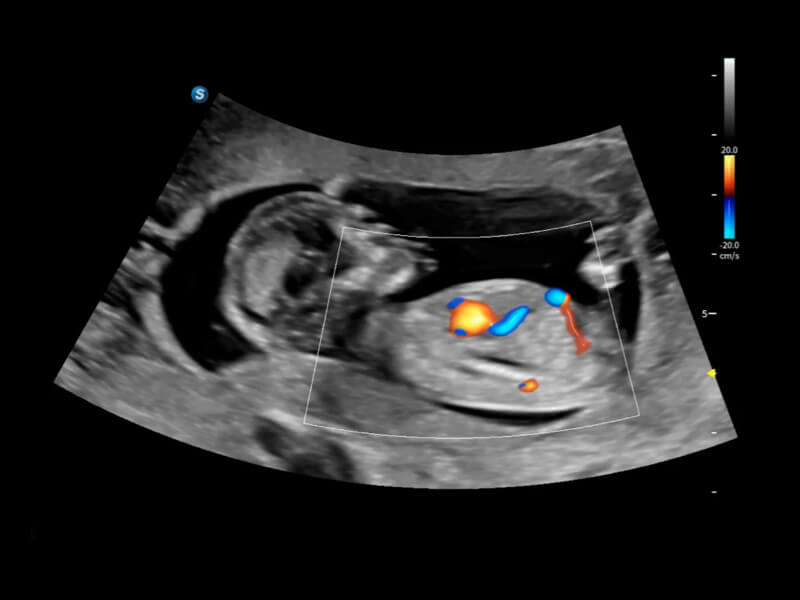

豐富的血流動(dòng)力學(xué)檢測(cè)技術(shù),可在不同醫(yī)療場(chǎng)景中高效捕捉血流信號(hào),助力臨床診療。

通過(guò)光照模型,使二維血流顯示出立體的效果,增加血流的敏感性、成束性,減少外溢??梢院推渌煌难骷夹g(shù)聯(lián)合使用,融合不同技術(shù)的優(yōu)勢(shì)。輕松應(yīng)對(duì)微小血管,增強(qiáng)血流的立體效果,提升視覺(jué)敏感性。

通過(guò)創(chuàng)新的Matrix E自適應(yīng)濾波算法,能有效濾除軟組織和噪聲信號(hào),最大限度保留超低速微細(xì)血流的信號(hào);結(jié)合超長(zhǎng)時(shí)間域算法,極大提升細(xì)微血流的敏感性和空間分辨率,更真實(shí)的反應(yīng)組織、包塊的血流灌注情況。